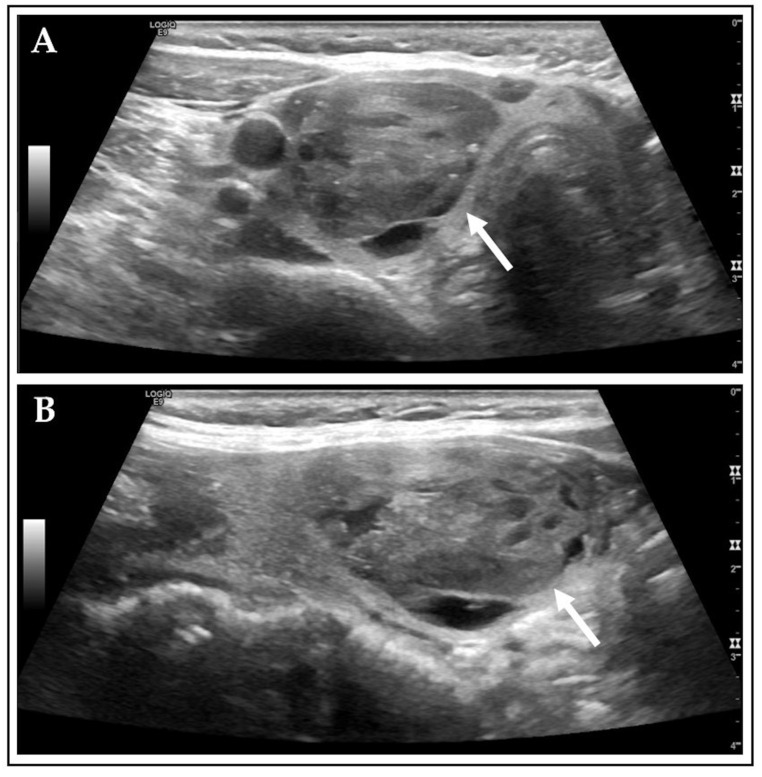

背景/目的:自主功能甲状腺结节(AFTNs)最常被诊断为良性。然而,它们在超声(US)风险分层系统(rss)中显示出很高的评级,该系统利用了传统静态图像捕获(SIC)文档的当前临床标准方法。本研究的目的是评估与SIC相比,cine loop (CL)视频序列的RSS评分和各自的细针细胞学(FNC)推荐值。方法:2015年11月至2023年11月期间,407例424例aftn患者被纳入这项单中心回顾性研究。对记录的US CL和SIC进行病变分析,并比较US特征、Kwak和ACR TIRADS、ACR FNC建议以及评估困难和伪影。采用SPSS软件中的Chi2检验和Spearman相关系数进行统计分析。p值< 0.05为显著性。结果:在比较CL和SIC时,观察到所有US特征、RSS评分和ACR FNC建议之间存在强到非常强的相关性(Spearman相关:各p < 0.001)。对于大约60%的aftn,给予ACR FNC推荐。Kwak TIRADS比ACR评分更符合aftn的良性本质。CL明显比SIC捕获更多的“回声灶”(ch2: p < 0.001)。伪影(图像质量差、声学阴影、矢状面不完全显示AFTN)在CL中更为常见,影响了~40%的AFTN,而在SIC中为~15% (χ 2: p < 0.05)。观察到CL和SIC之间的评估置信度弱相关,SIC优于CL (Spearman相关:各p < 0.001)。结论:在RSS评分和ACR FNC建议方面,CL和SIC之间存在很强的相关性。与ACR相比,Kwak是AFTNs良性特征的优秀代表。然而,CL提供了更详细的信息,同时降低了观察者的信心和更多的工件。具体的操作员培训和技术改进,包括人工智能的实施,可以提高未来的图像质量。

Background/Objectives: Autonomously functioning thyroid nodules (AFTNs) are most frequently diagnosed as benign. However, they show high ratings in ultrasound (US) risk stratification systems (RSSs) that utilize the current clinical standard methodology of conventional static image capture (SIC) documentation. The objective of this study was to evaluate the RSS ratings and respective fine needle cytology (FNC) recommendations of cine loop (CL) video sequences in comparison to SIC. Methods: 407 patients with 424 AFTNs were enrolled in this unicentric, retrospective study between 11/2015 and 11/2023. Recorded US CL and SIC were analyzed lesion-wise and compared regarding US features, Kwak and ACR TIRADS, ACR FNC recommendations, as well as assessment difficulties and artifacts. Statistical analyses were conducted using the Chi2 test and Spearman's correlation coefficient in SPSS software. p-values < 0.05 were considered significant. Results: Strong to very strong correlations were observed for all US features, RSS ratings, and ACR FNC recommendations (Spearman's correlation: each p < 0.001), comparing CL and SIC. For >60% of the AFTNs, ACR FNC recommendation was given. Kwak TIRADS were more consistent with the benign nature of AFTNs than the ACR ratings. CL captured significantly more "echogenic foci" than SIC (Chi2: p < 0.001). Artifacts (poor image quality, acoustic shadowing, sagittal incompletely displayed AFTN) were significantly more common on CL, affecting ~40% of AFTNs, compared to ~15% on SIC (Chi2: each p < 0.05). Weak correlation was observed for assessment confidence between CL and SIC, with SIC outperforming CL (Spearman's correlation: each p < 0.001). Conclusions: A strong correlation was identified between CL and SIC in terms of RSS ratings and ACR FNC recommendations. Kwak is a superior representative of the benign character of AFTNs than ACR. However, CL provided more detailed information while being associated with decreased observer confidence and more artifacts. Specific operator training and technical improvements, including AI implementation, could improve image quality in future.